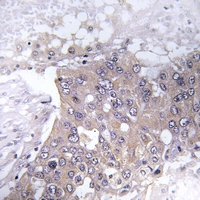

IHC (Immunohiostchemistry)

(Dilution: WB: (1/500 - 1/1000), IH (1/50 - 1/200)Immunohistochemical analysis of JAK2 (pY221) staining in human liver cancer formalin fixed paraffin embedded tissue section. The section was pre-treated using heat mediated antigen retrieval with sodium citrate buffer (pH 6.0). The section was then incubated with the antibody at room temperature and detected using an HRP conjugated compact polymer system. DAB was used as the chromogen. The section was then counterstained with haematoxylin and mounted with DPX.)